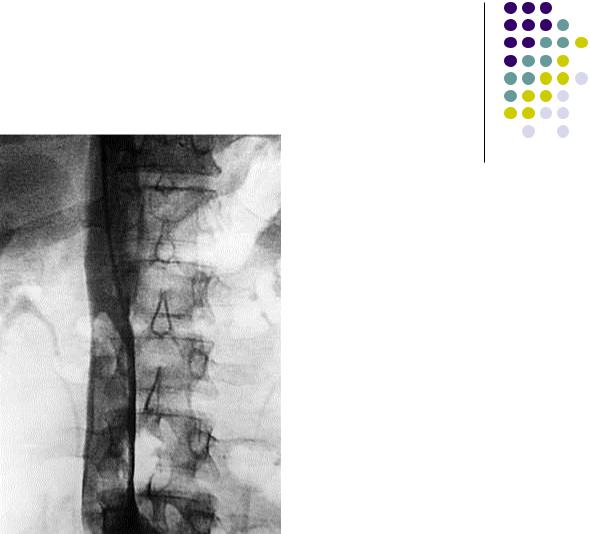

Рентгенконтрастная илио-каваграфия

Флотирующий тромб нижней полой вены